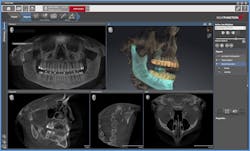

My experience with Galileos has been an evolutionary process. Seven years ago, I utilized CBCT simply to provide a 3-D image for diagnostics. Since then, the images have improved in clarity and resolution due to constant improvements in reconstructive algorithms and constant updates in software. In addition, the Galaxis software has functionally evolved from providing the essential diagnostic tools to providing integration with CEREC (GCI) for simultaneous prosthetic and surgical planning.

New additions include a vast implant library with abutments, volumetric clipping, metal artifact reduction (MAR) algorithm for improved imaging quality for our heavily restored patients, the Integrated Face Scanner (IFS) for Galileos Comfort Plus, and now JMT and airway analysis with SICAT. The combination of GCI, the IFS, and JMT provide us a complete "virtually integrated patient."

Rather than a two-dimensional X-ray, the "virtually integrated patient" is a Sirona concept that allows patients to identify themselves and their conditions with their own faces. The combination of three-dimensional X-ray with an image of the patient's own face helps patients understand the dentist's suggestions more quickly. Obviously, this leads to higher acceptance of the proposed therapy. The treatment modalities have evolved to include traditional surgical guides, Galileos-CEREC integration surgical guides, Optiguide by SICAT (centrally milled guides), and now Digital Orthotics and Splints by SICAT.

In my practice, a routine new-patient exam may include a Galileos CBCT scan. This is the foundation of my examination process. The Galaxis imaging software by Sirona is specifically tailored to enhance dental workflow. There is a significant reduction in time for our new-patient exam process due to the comprehensive nature of the data within the CBCT scan. The combination of bitewing X-rays and CBCT allows diagnostics for all facets of dentistry: restorative, periodontics, orthodontics, oral surgery, endodontics, and implantology. Each are defined with one scan from Sirona's Galileos CBCT.